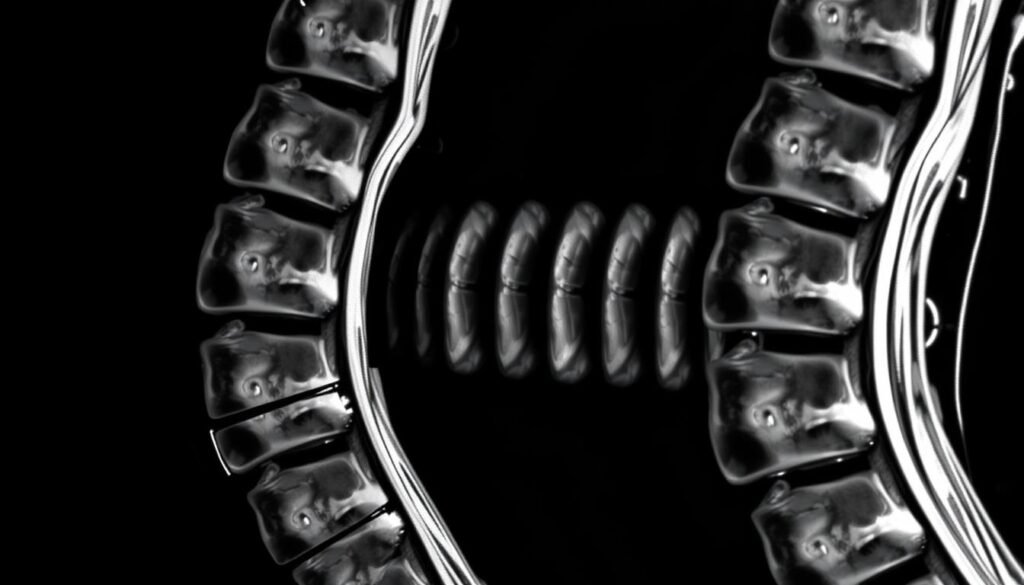

MRT-Aufnahme einer Wirbelsäule mit deutlich sichtbarer Bandscheibendegeneration (Pfeil)

Die Diagnose einer Bandscheibendegeneration erfolgt durch eine Kombination aus Anamnese, körperlicher Untersuchung und bildgebenden Verfahren:

Die MRT ist besonders wertvoll, da sie nicht nur die Bandscheiben selbst, sondern auch umliegende Strukturen wie Nerven, Rückenmark und Wirbelgelenke darstellen kann. So können auch Folgeerkrankungen der Bandscheibendegeneration erkannt werden.